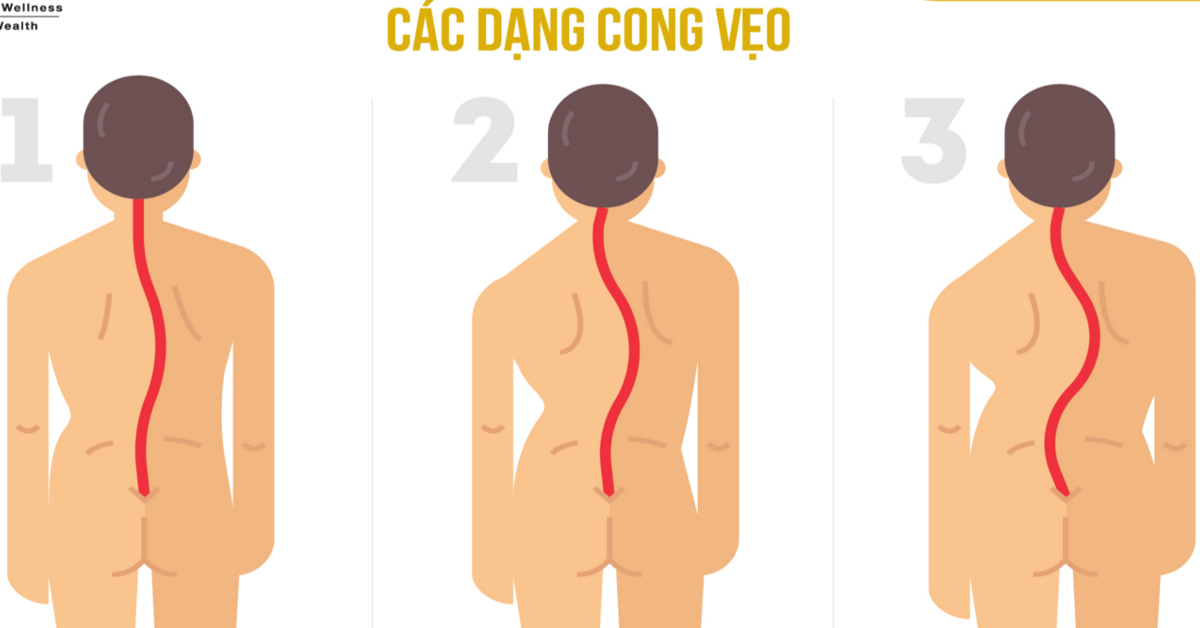

Cong vẹo cột sống là tình trạng cột sống bị cong hoặc vẹo sang một bên, thường là hình chữ “S” hoặc “C”, đường cong có thể đổ về phía trước hoặc phía sau (gù cột sống), cột sống lệch sang một bên (cong cột sống) tùy vào nguyên nhân mắc bệnh của từng người. Cột sống bình thường có độ cong nhẹ để hỗ trợ chức năng vận động và hấp thụ chấn động, nhưng khi bị cong vẹo, các đốt sống không còn nằm trong một đường thẳng bình thường nữa. Tình trạng này có thể gây ra đau lưng, mất cân bằng cơ thể, và các vấn đề về hô hấp.

Đây là một loại bệnh có thể cải thiện dần theo thời gian. Trong những trường hợp cột sống cong vẹo mức độ nhẹ, không làm ảnh hưởng đến sinh hoạt thường ngày, hoặc ảnh hưởng nghiêm trọng đến sức khỏe thể chất, người bệnh chỉ cần thực hiện những bài tập lưng nhẹ nhàng đã có thể cải thiện và phục hồi tình trạng dần theo thời gian.Các đường cong là một phần hiển nhiên của cấu trúc cột sống. Độ cong được xem là tự nhiên khi hình dáng xương nhìn nghiêng có hình chữ S cong mềm mại và khi quan sát trực diện từ phía sau sẽ thấy cột sống thẳng.

Cong vẹo cột sống được xem là một loại rối loạn cột sống được xác định bởi độ cong bất thường của cột sống. Tình trạng này thường xảy ra ở phần lồng ngực hoặc xương sườn.